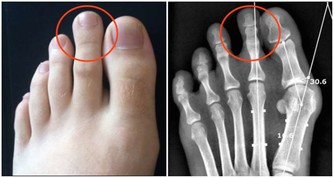

不曉得大家有沒有指甲就會不小心嵌入肉裡的經驗?

以前小時候不太會剪腳趾甲,就很容易會變成這種狀況,

指甲嵌進去肉裡之後就會開始發腫、發炎,甚至還會化膿!

這樣就可能導致細菌進入傷口,甚至造成嚴重的感染!

但現在不用擔心了!這次要來教大家 10 個在家就可以處理的小妙招,讓你可以自己解決這個棘手的問題。

不過如果情況真的太嚴重,還是要請專業的醫生來協助哦!